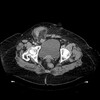

139

Inguinal hernia

What pathology is shown here?

141

Inguinal hernia ## Footnote -Seeing large amount of bowel loops hanging out of inguinal canal